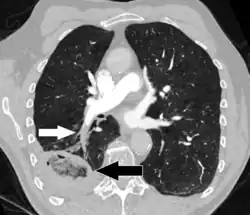

CT pulmonary angiography

CT pulmonary angiography (CTPA) is a pulmonary angiogram obtained using computed tomography (CT) with radiocontrast rather than right heart catheterization. Its advantages are that it is accurate, it is non-invasive, it is more often available, and it may identify other lung disorders in case there is no pulmonary embolism. The accuracy and non-invasive nature of CTPA also make it advantageous for people who are pregnant.[61]

Assessing the accuracy of CT pulmonary angiography is hindered by the rapid changes in the number of rows of detectors available in multidetector CT (MDCT) machines.[62] According to a cohort study, single-slice spiral CT may help diagnose detection among people with suspected pulmonary embolism.[63] In this study, the sensitivity was 69% and specificity was 84%. In this study which had a prevalence of detection was 32%, the positive predictive value of 67.0% and negative predictive value of 85.2%. However, this study's results may be biased due to possible incorporation bias, since the CT scan was the final diagnostic tool in people with pulmonary embolism. The authors noted that a negative single-slice CT scan is insufficient to rule out pulmonary embolism on its own. A separate study with a mixture of 4-slice and 16-slice scanners reported a sensitivity of 83% and a specificity of 96%, which means that it is a good test for ruling out a pulmonary embolism if it is not seen on imaging and that it is very good at confirming a pulmonary embolism is present if it is seen. This study noted that additional testing is necessary when the clinical probability is inconsistent with the imaging results.[64] CTPA is non-inferior to VQ scanning, and identifies more emboli (without necessarily improving the outcome) compared to VQ scanning.[65]